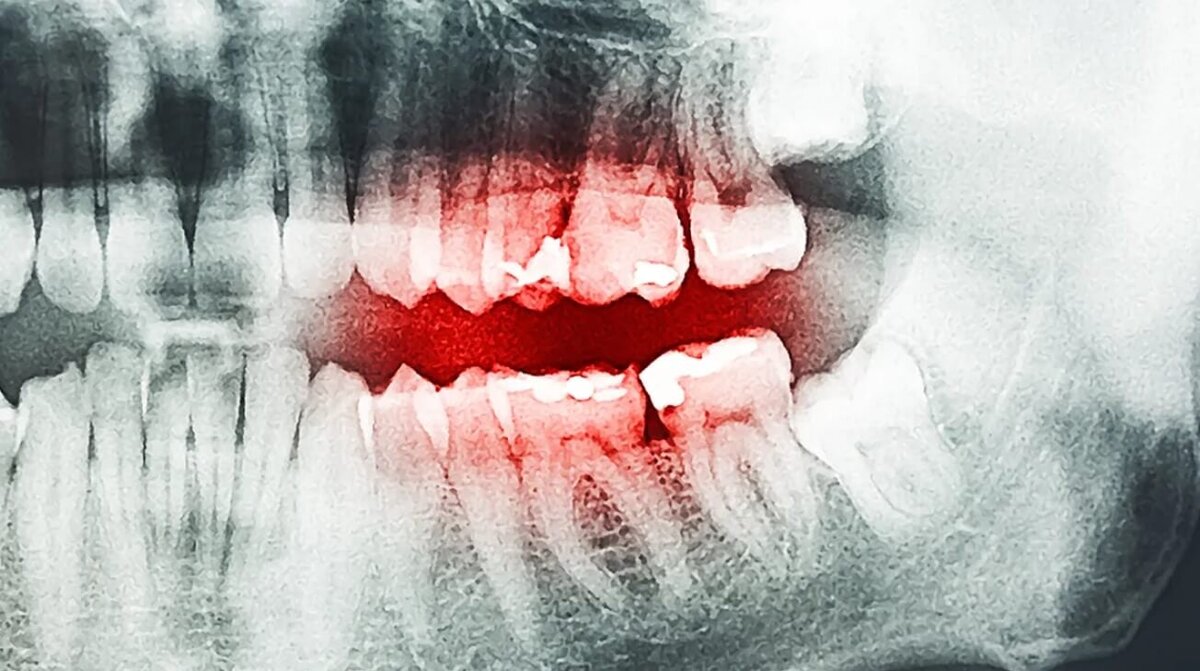

В 1800-е годы несколько жителей США обратились к стоматологам с неожиданной жалобой — у них во рту лопнули зубы. Так, в 1817 году, священнослужитель из штата Пенсильвания начал испытывать настолько сильную зубную боль, что даже пытался спрятать свою голову в земле и окунал ее в ледяную воду. Мужчина перестал мучиться только после того, как услышал треск в голове и его зуб разорвался на осколки. После этого он спокойно уснул на целый день, и только потом об этом случае стало известно широкой общественности. Это был не единственный случай, когда больной зуб жителя 19 века разорвался на несколько частей и принес долгожданное облегчение. Современные стоматологи не могут точно сказать, почему зубы некоторых людей взрывались, но у них есть парочка правдоподобных предположений. Интересный факт: страх перед стоматологами и лечением зубов принято называть одонтофобией, дентофобией или стоматофобией. Эта фобия встречается у каждого четвертого человека в мире и связана с негативным опытом лечения

В 1800-е годы несколько жителей США обратились к стоматологам с неожиданной жалобой — у них во рту лопнули зубы. Так, в 1817 году, священнослужитель из штата Пенсильвания начал испытывать настолько сильную зубную боль, что даже пытался спрятать свою голову в земле и окунал ее в ледяную воду. Мужчина перестал мучиться только после того, как услышал треск в голове и его зуб разорвался на осколки. После этого он спокойно уснул на целый день, и только потом об этом случае стало известно широкой общественности. Это был не единственный случай, когда больной зуб жителя 19 века разорвался на несколько частей и принес долгожданное облегчение. Современные стоматологи не могут точно сказать, почему зубы некоторых людей взрывались, но у них есть парочка правдоподобных предположений.

По данным издания IFL Science, ситуация со священнослужителем была настолько серьезной, что из-за нестерпимой зубной боли он «вонзал голову в землю как разъяренный зверь и погружал ее в холодную воду». По крайней мере, именно так его мучения описал дантист У. Х. Аткинсон в отчете за 1860 год. Мучения завершились только спустя несколько месяцев, когда в девять часов утра мужчина услышал во рту резкий треск и его зуб разорвался на части. После дневного сна священнослужитель чувствовал себя гораздо лучше и выздоровел.

Такие же случаи были зарегистрированы в 1830 и 1855 году. У людей наблюдалась нарастающая зубная боль, после чего она становилась непереносимой. Облегчение приходило только после того, как зуб с треском распадался на части — после этого «взрыва», людям мгновенно становилось лучше. Важно отметить, что о таких случаях сообщал не один дантист, а несколько специалистов по зубам, которые вряд ли были знакомы друг с другом.

Например, о пациенте с такой проблемой в 1874 году писал дантист Фелпс Хиблер:

Внезапно, без каких-либо симптомов, кроме предыдущей сильной боли, правый нижний первый моляр лопнул настолько сильно, что чуть не сбил женщину с ног.

Случаи взрыва зубов фиксировались в США до 1920-х годов, а потом прекратились. К сожалению, современные стоматологи не имеют в своем распоряжении остатки этих зубов, поэтому не могут точно сказать, почему они лопнули. Но у них есть несколько предположений, из-за чего это могло случиться.

Первая версия гласит, что причиной взрыва гниющих зубов могло стать накопление внутри них газов. Действительно, в больных зубах могут накапливаться газы, однако они вряд ли оказывали настолько высокое давление, чтобы разорвать зубы на части. Считается, что зубы являются самыми прочными частями человеческого организма. Они не прочнее алмаза, но вполне могут конкурировать по твердости с некоторыми видами металлов.

Более правдоподобное предположение выдвинула профессор неорганической химии Андреа Селла. По ее словам, зубы живших в 1800-е годы были взрывоопасными из-за материалов, которые использовались для пломбирования зубов. Некоторые дантисты тех времен заполняли полости различными металлами, начиная с нежелательного олова и заканчивая еще более опасным свинцом. Если во время лечения зуба было использовано два вида металла, он мог превратиться в некое подобие батареи и взорваться или загореться из-за спонтанного электролиза.

Скорее всего, взрывоопасность зубов жителей 19 века была связана с особенностями стоматологии тех времен. Сегодня в медицине используются только проверенные материалы, которые не наносят вреда организму. Так что бояться лечения зубов, во многом, уже не актуально — учитывая использование сильных обезболивающих, все происходит быстро и без особой боли.